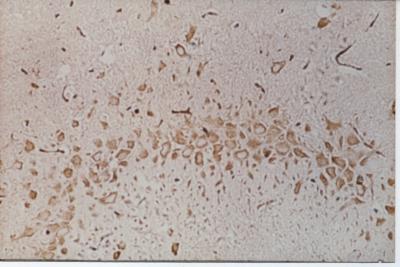

Neuroprotection by ischemic preconditioning has been confirmed by many studies, but the precise mechanism remains unclear. In a study released in the Neural Regeneration Research (Vol. 9, No. 11, 2014), Dr. Yong Liu and co-workers from Tongji Hospital Affiliated to Tongji Medical College, Huazhong University of Science and Technology, China performed cerebral ischemic preconditioning in rats by simulating a transient ischemic attack, and explored the mechanism underlying the neuroprotective effect of ischemic preconditioning. Researchers discovered that the infarct volume became significantly smaller underwent preconditioning. Furthermore, vascular endothelial growth factor immunoreactivity was considerably greater in the hippocampal CA3 region of preconditioned rats. Their results suggest that the protective effects of ischemic preconditioning on focal cerebral infarction are associated with upregulation of vascular endothelial growth factor.

Article: " Neuroprotective effect of ischemic preconditioning in focal cerebral infarction: relationship with upregulation of vascular endothelial growth factor," by Yong Liu1, 2, Suiqiang Zhu1, Yunfu Wang2, Jingquan Hu2, Lili Xu2, Li Ding2, Guangjian Liu2 (1 Department of Neurology, Tongji Hospital Affiliated to Tongji Medical College, Huazhong University of Science and Technology, Wuhan, Hubei Province, China; 2 Department of Neurology, Taihe Hospital Affiliated to Hubei University of Medicine, Shiyan, Hubei Province, China) Liu Y, Zhu SQ, Wang YF, Hu JQ, Xu LL, Ding L, Liu GJ. Neuroprotective effect of ischemic preconditioning in focal cerebral infarction: relationship with upregulation of vascular endothelial growth factor. Neural Regen Res. 2014;9(11):1117-1121.